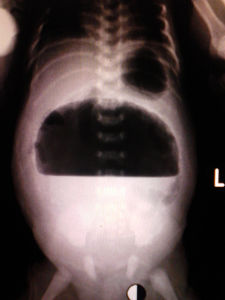

(三)游離氣腹型出生時腸穿孔仍存在,未能被粘連所包裹,新生兒吞咽的氣體、奶汁及胃腸道內分泌物進入腹腔,迅速發生細菌性腹膜炎及大量腹水,病情重危,嘔吐、拒食、便秘、體溫低下,呈中毒性休克,嚴重者影響呼吸而出現呼吸困難、紫紺等症狀,腹脹如球,觸之有氣囊感。叩診濁音。腹部平片顯示巨大氣液平面橫貫全腹,膈下大量積氣,肝臟下垂,全腹部不透明,僅見少量腸道氣體,鈣化斑塊可在腹腔任何部位。腹膜鞘狀突未閉者,可有陰囊或陰唇水腫,甚至鈣化斑塊。

在嬰兒出生前亦能作出診斷,多因伴有腸梗阻而阻礙胎兒吞咽羊水的運行,於是孕婦發生羊水過多徵象,X線檢查顯示胎兒腹腔內有鈣化斑塊,即可確診。如生後有腹膜炎或腸梗阻症狀,進行腹部平片檢查顯示有特徵性的鈣化陰影存在,就可確定診斷。但如果未見鈣化影,當然也不能否定診斷。如攝片條件合適,鈣化影的出現率應該是很高的。